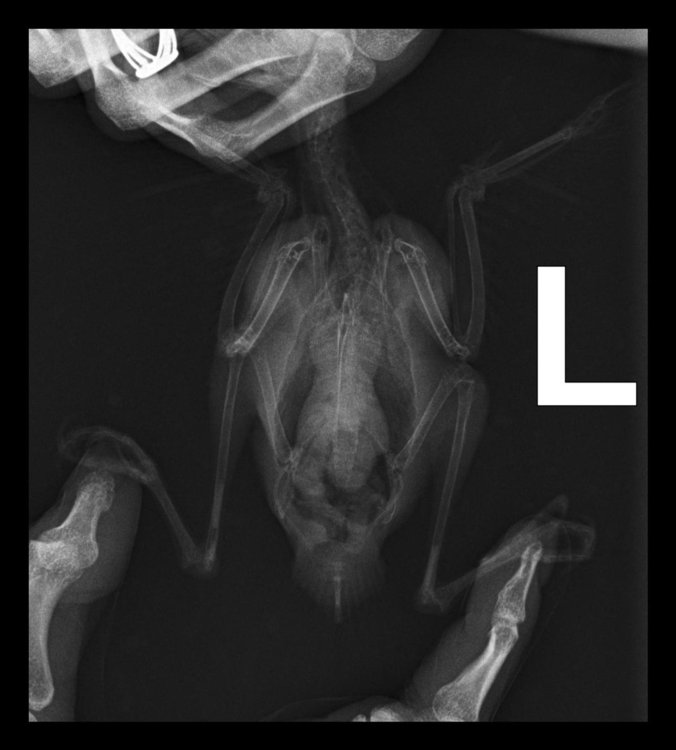

Необходима консультация. Попугай какарик (самка) стала себя странно вести, пропала активность, сидит в темных местах, и перестала летать.

Были на приёме у орнитолога, по внешнему осмотру птица здорова, направили на рентген.

Рентгеновский снимок прислали, но без заключения, в ходе телефонного разговора с орнитологом оказалось, что имеется кистозное образование и недостаток кальция, из лечения был прописан мелоксидол и кальций.

Скажите пожалуйста, что это за образование и насколько все серьезно?

Орнитолог сказал, что пока просто наблюдение. Очень переживаю, возможно кто-нибудь сможет расшифровать снимок и высказать своё мнение.

( после приема лекарств птица практически такая же активная, как и была, летает, но довольно редко)

E589DA2C-389E-4B17-8E07-E86340FA53D9.jpeg